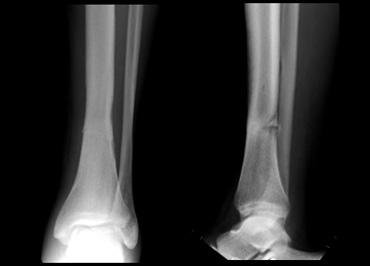

Hình bên trái là một nam giới 50 tuổi, vốn có lối sống ít vận động.

Ông tham gia một cuộc thi đi bộ 10 dặm mà không có bất kỳ sự chuẩn bị tập luyện nào trước đó.

Cơn đau ở cẳng chân xuất hiện từ từ và cuối cùng ông không thể tiếp tục đi bộ.

X-quang cho thấy gãy xương do stress ở đầu dưới xương chày.

Vận động quá mức trong thời gian ngắn là nguyên nhân thường gặp của gãy xương do stress.